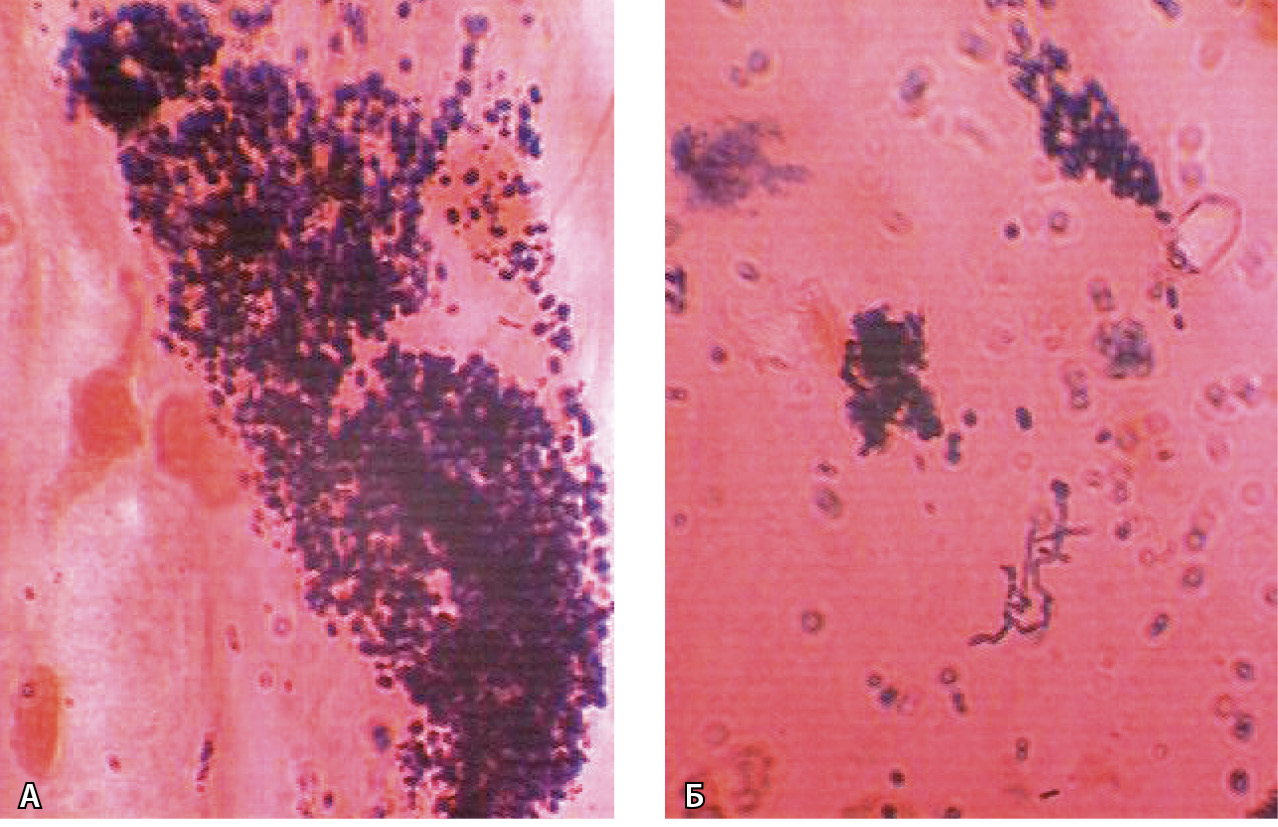

Одна из основных функций кислоты в желудке – защита от желудочно-кишечных инфекций. У пациентов, получающих длительную терапию ИПП, развиваются выраженные изменения в кишечном микробиоме, характеризующиеся отклонением от его нормального состава, повышенным ростом в дистальных отделах кишечника представителей флоры верхних ее отделов. На фоне гипохлоргидрии повышается возможность развития кишечных инфекций, вызванных Salmonella, Shigella, Campylobacter или Escherichia coli [20], а также активизируется грибковая флора [21] (рис. 5).

Рис. 5. Дрожжеподобные грибы (А) и псевдомицелий Candida albicans (Б) в желудочной слизи на фоне приема ингибиторов протонной помпы. Окраска по Граму; × 1200 (из личного архива С.Г. Хомерики)